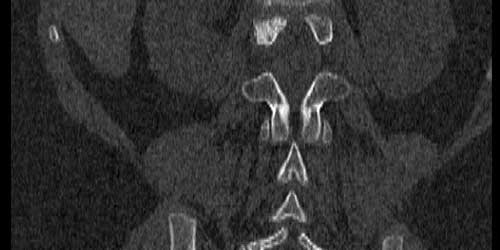

- Manyetik rezonans görüntüleme (MRG). MRG, omurga, omurilik ve sinirlerinizin doğru görüntülerini üretmek için güçlü bir mıknatıs ve radyo dalgaları kullanır. MRG genellikle vertebral tümörleri teşhis etmek için tercih edilen testtir. Belli dokular ve yapıları vurgulamaya yardımcı olan bir kontrast madde, test sırasında ayağınızdaki veya önkoldaki bir damar içine enjekte edilebilir.

- Bilgisayarlı tomografi (BT) taraması. MRG yumuşak dokuları daha ayrıntılı gösterirken BT kemik yapıları göstermede daha üstün ve kullanışlıdır. BT taraması MRG ile kombinasyon halinde kullanılabilir. Ayrıca nereden kaynaklandığı bilinmeyen metastaz hastalarında primer odağı saptamak için akciğer, karın (batın) tomografisi çekilir. Metastatik hastalarda başka bir omurga lokalizasyonunda da lezyon olabilme ihtimalinden dolayı (%15) görüntüleme yöntemleri tüm omurgayı içerecek şekilde çekilmelidir.